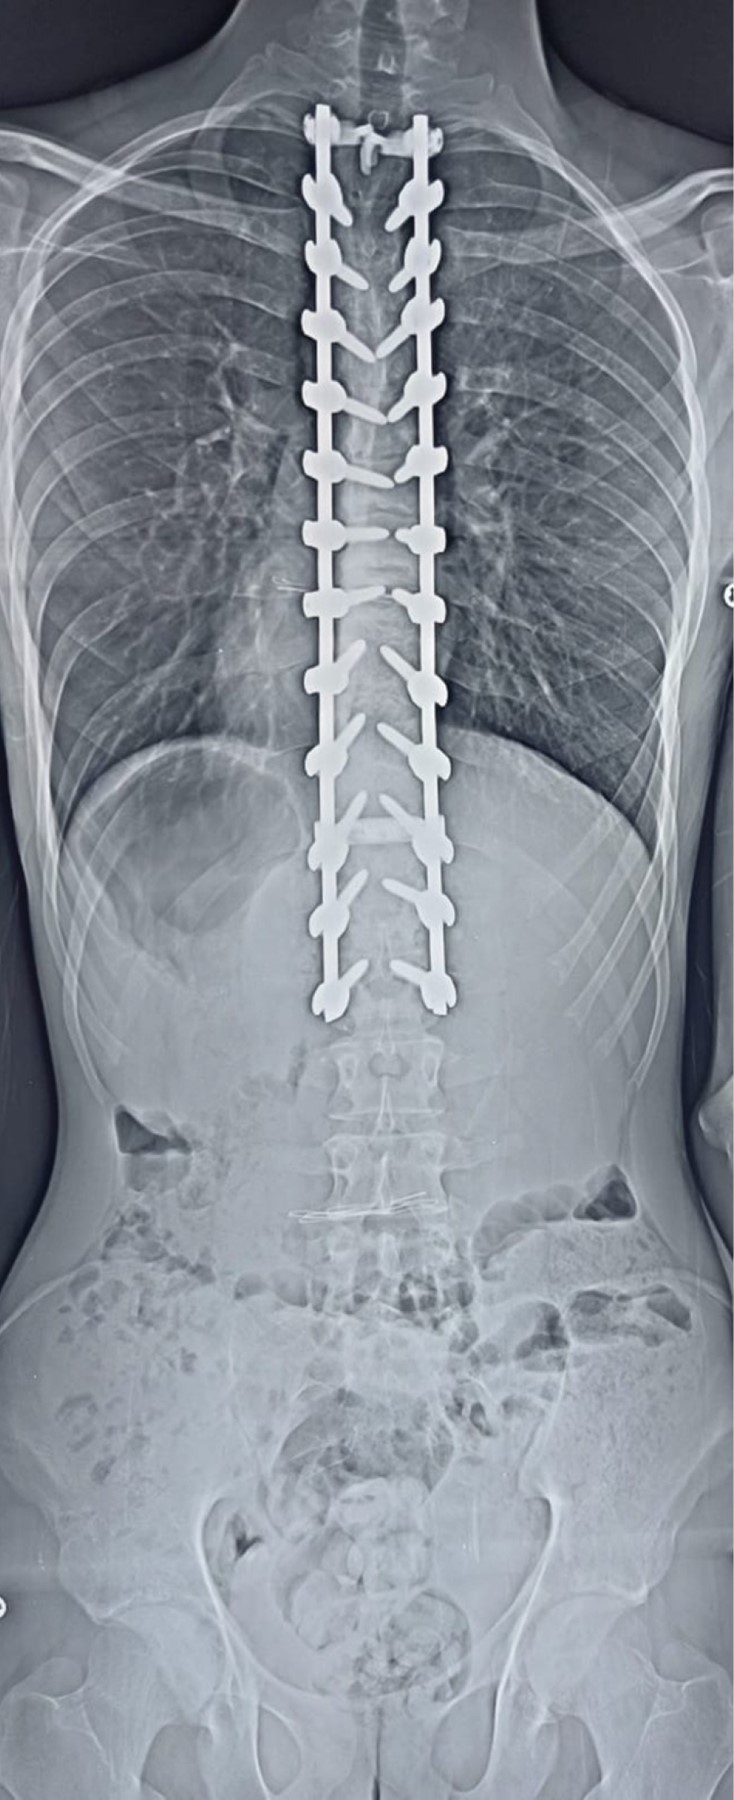

Paciente masculino de 22 años de edad y sin antecedentes de relevancia, el cual se presenta a consulta por deformidad, la cual le crea inseguridad estética y dolor recurrente de región torácica. Se solicitan radiografías anteroposterior (AP) y lateral panorámicas de columna, se detecta una deformidad de 105° de cifosis torácica (Figuras 1 y 2). Se propone al paciente realización de instrumentación posterior y fusión con corrección de curva torácica, quien acepta el tratamiento. Se realiza cirugía de instrumentación y fusión posterior exclusiva de T2 a L2 con tornillos poliaxiales mediante neuronavegación con O-ARM™ y neuromonitoreo (Figuras 3, 4 y 5). El paciente muestra buena evolución inmediata con una pérdida sanguínea menor de 200 ml durante las tres horas de procedimiento quirúrgico, además de buena evolución durante el primer, tercer y sexto mes con desaparición del dolor y corrección de curva a 40°(Figuras 6 y 7).